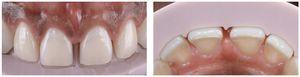

Se retira el dique de goma y se corrige la oclusión mediante un sistema de pulidores de diamante para cerámica. El tejido gingival sano estaba estable al cabo de dos semanas (figs. 35 y 36). Las figuras 37 y 38 muestran la sonrisa del paciente seis meses después del cementado.

Fig. 36. La situación al cabo de tres meses.

Figs. 37 a 40. La situación final al cabo de seis meses.